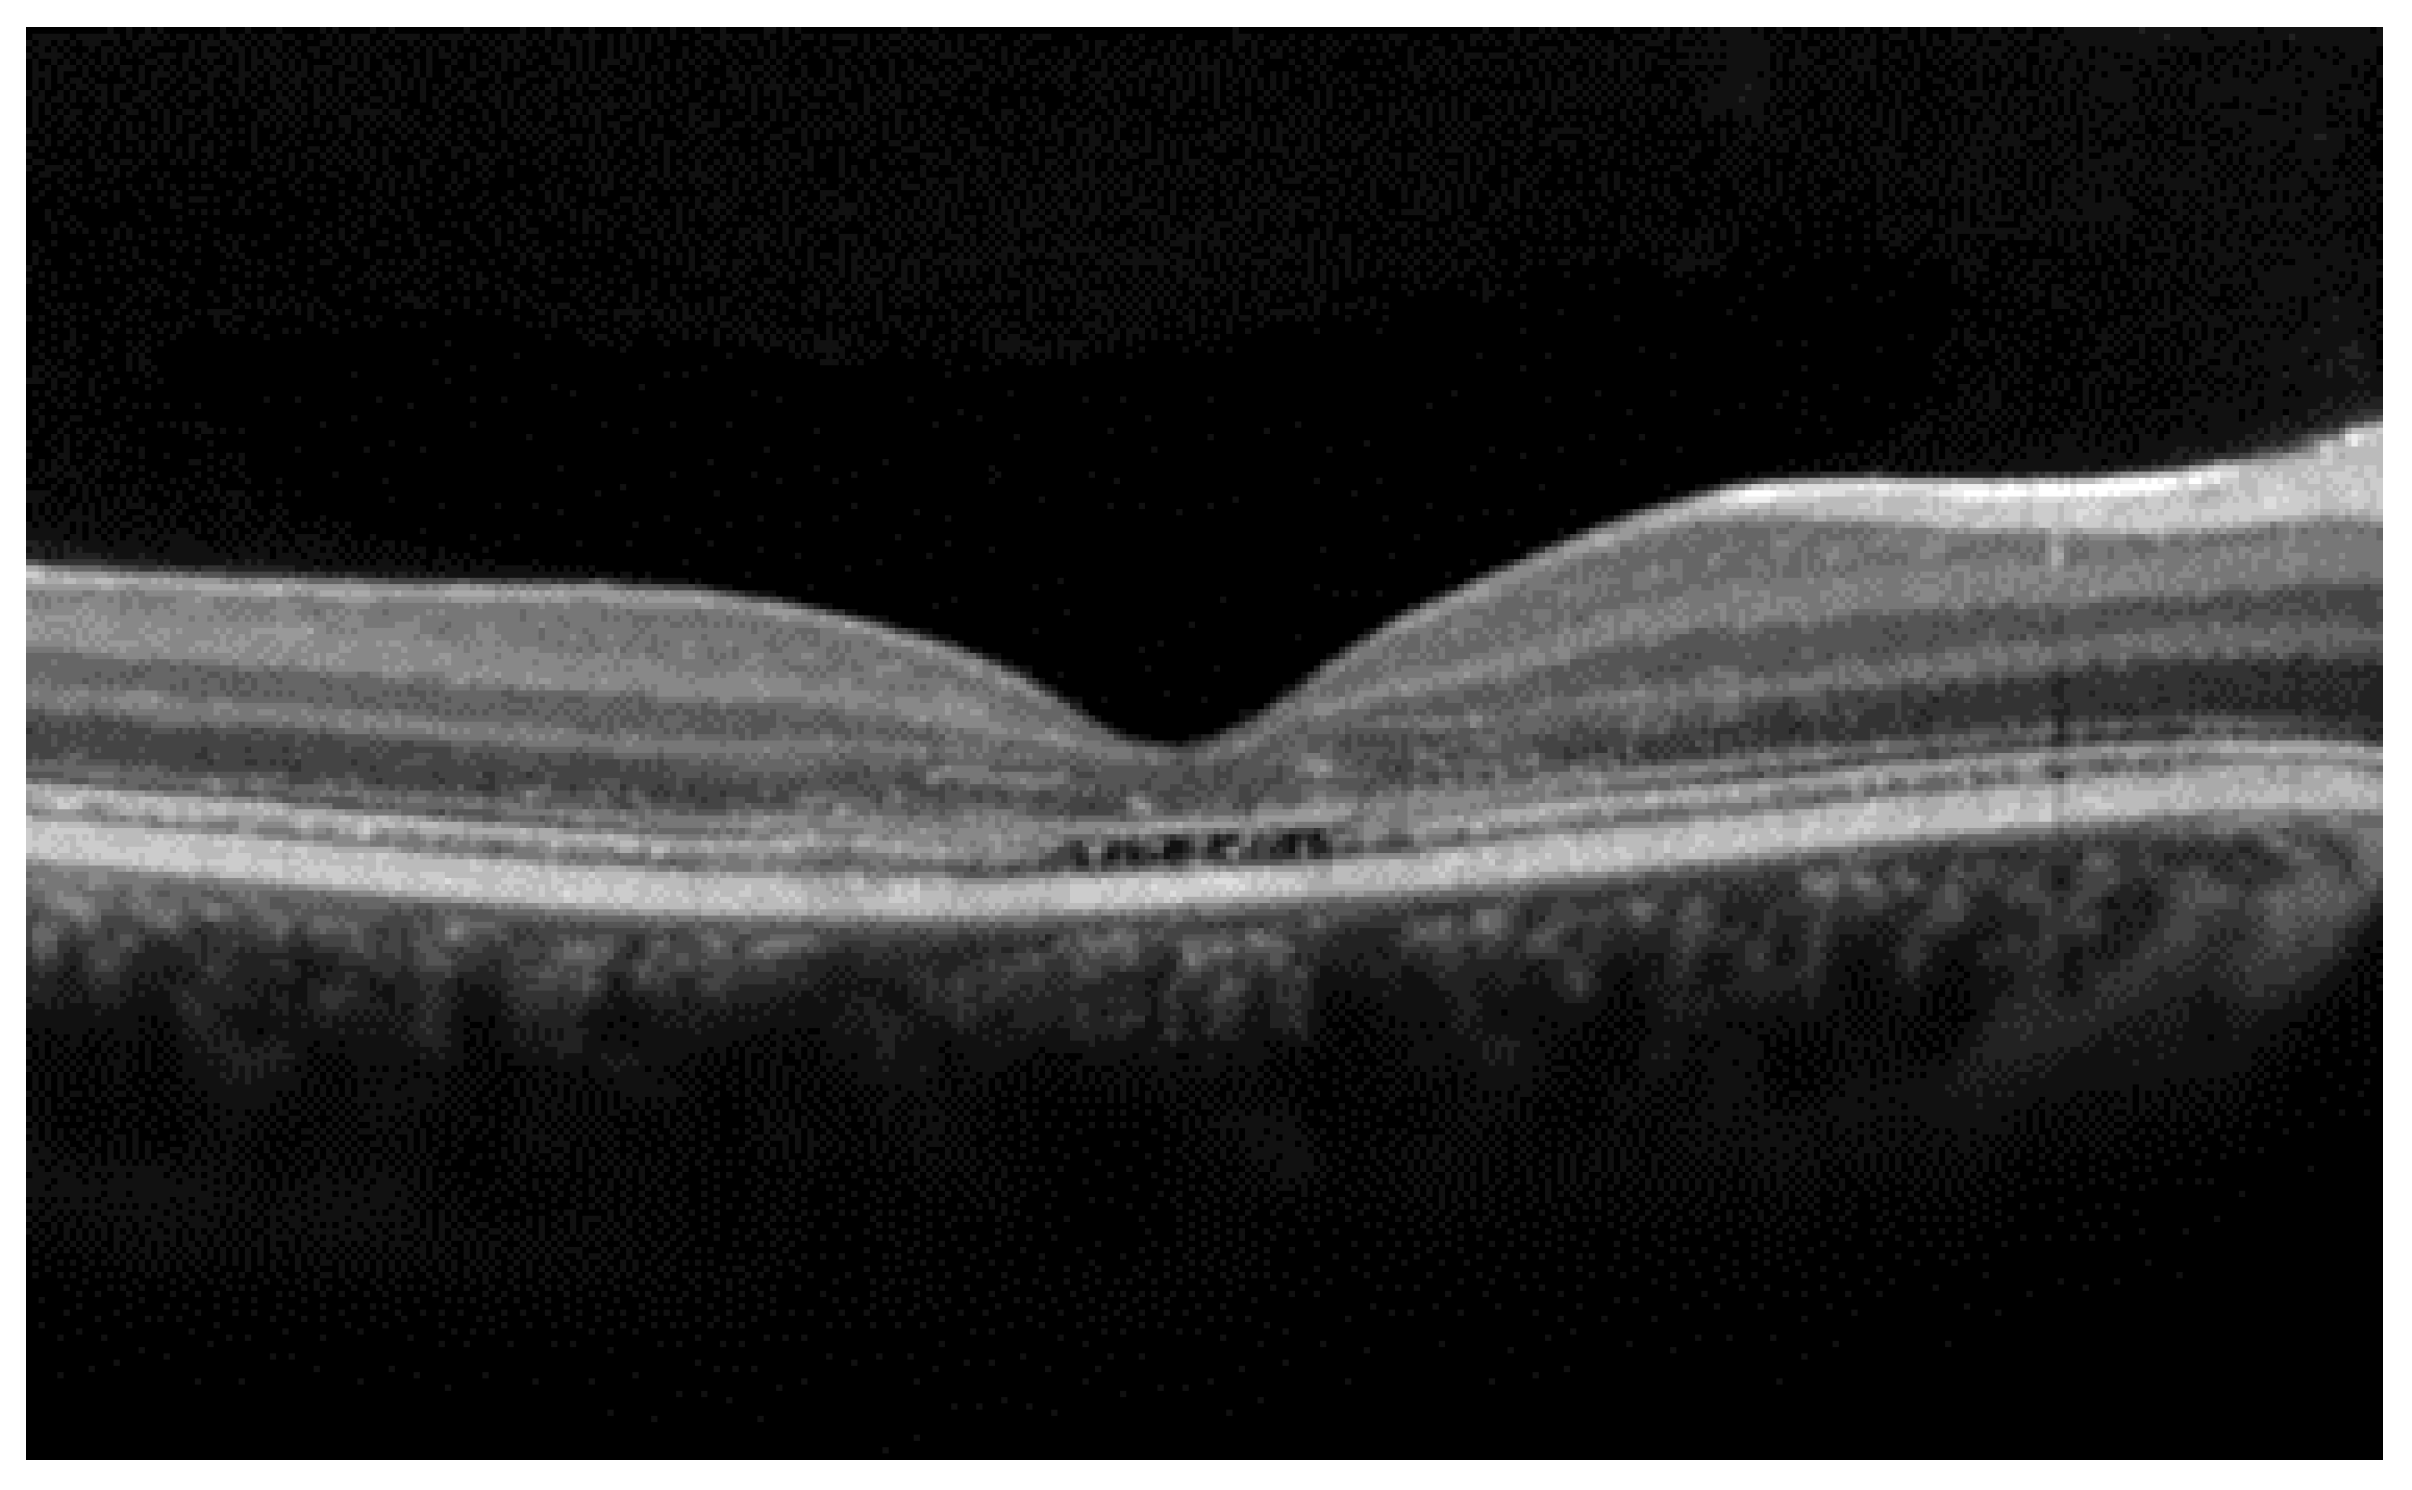

- The integrity of the EZ is the most closely linked factor to a decline in visual acuity. Its intensity, both in the affected areas and the surrounding regions, is attenuated in patients who show disease progression, and expansion of the disrupted EZ region is linked to a higher probability of visual acuity loss. Additionally, it is worth noting that many patients exhibit a central region with a preserved EZ, referred to as an optically preserved islet or OPI, which is associated with improved visual outcomes [29]. However, it is essential to recognize that EZ loss tends to occur in later stages and is typically associated with already significant visual impairment.

- Another noteworthy OCT biomarker is the measurement of ONL thickness, which can serve as an indicator of early photoreceptor degeneration. Irrespective of the clinical stage, BVMD patients exhibit reduced ONL thickness compared to healthy individuals [30]. Also, there is a correlation between ONL thickness and both BCVA and retinal sensitivity. Therefore, ONL thickness could prove to be a more valuable quantitative measure for assessing the anatomical loss of photoreceptors and the decline in macular function.

| Best vitelliform macular dystrophy |